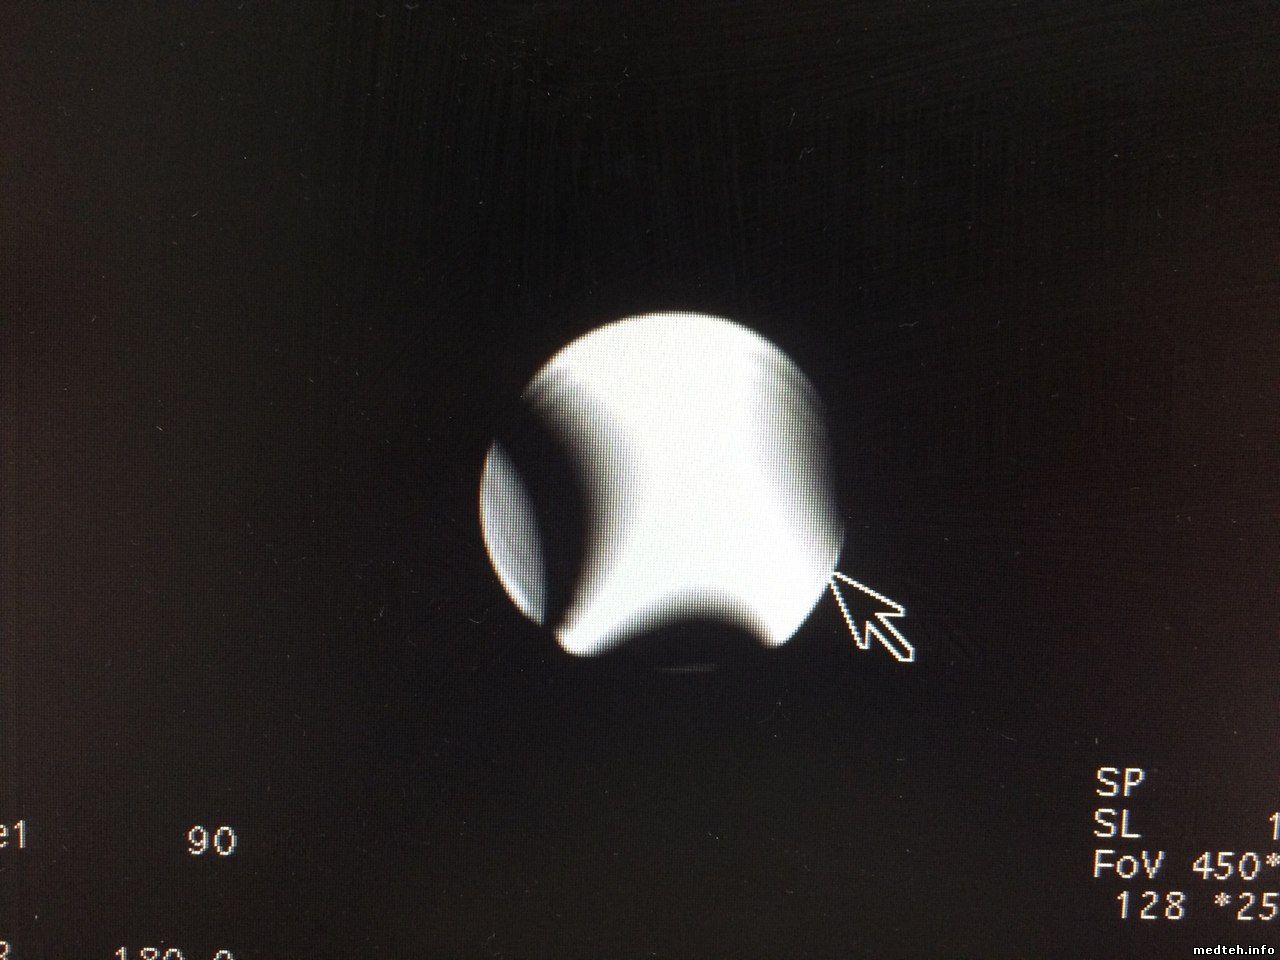

А вот нет... Теперь эджастится, правда картинка заставляет желать лучшего...

9115098.jpg (152.2 Kb)